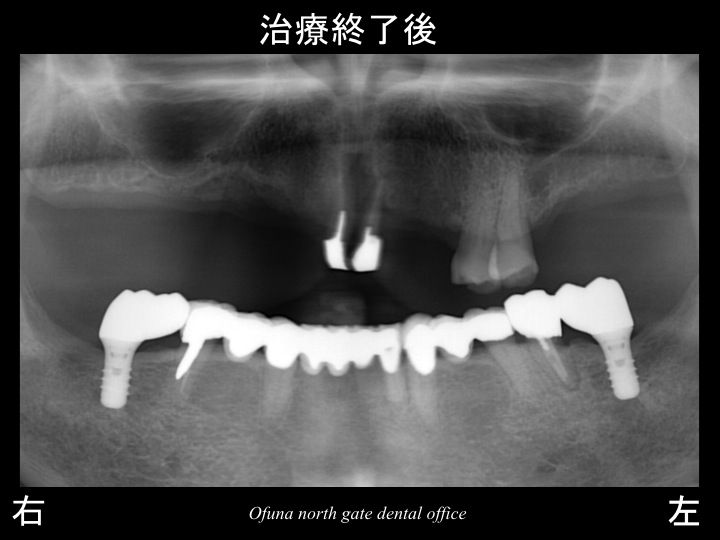

そこで最終的なインプラント治療計画は、以下のようになりました。

下顎の左右の奥歯に1本づつ行うのです。

これにより、その手前の神経のない歯に負担が加わるのを少なくできます。

もちろん義歯を使用しないで、奥歯で噛めることにもなります。

上顎は、義歯で対応!

下顎の前歯部は、固定をかねてブリッジで対応!

下顎の奥歯は、最小限の範囲でインプラントで対応!

これにより下顎の神経がない歯の負担を最小限にできたことが

将来性を高めることにつながるのです。